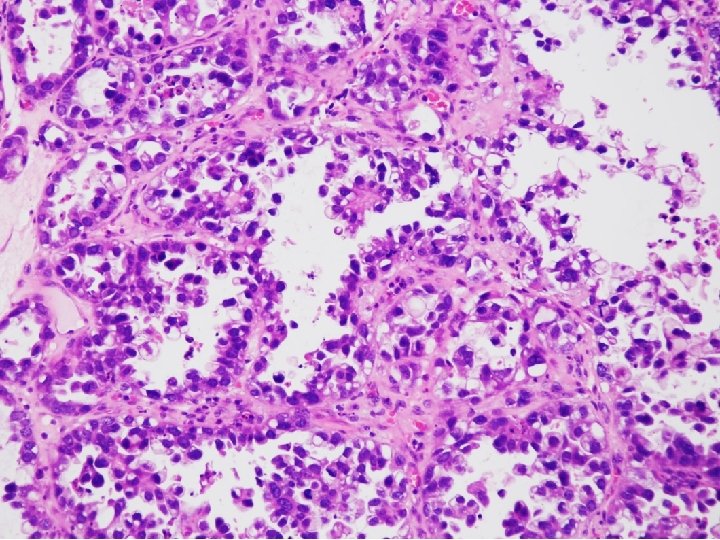

• Clear cell carcinomas present marked cellular and nuclear pleomorphism; they often have bizarre nuclei and abundant, pale cytoplasm Color Atlas of DDx in Exfoliative and Aspiration Cytopathology, Kini

CYTOPATHOLOGIC FEATURES OF CLEAR CELL CARCINOMA • Arrangement – Cells are isolated, in loosely cohesive groups and in syncytial tissue fragments; hobnail pattern may be present • Cells – Medium to large with poorly defined cell borders; moderate to high N/C ratios; round, polygonal to hobnail type • Nuclei – Large, round, often eccentric, very pleomorphic; coarsely granular to smudgy chromatin; nucleoli are inconsistent; multinucleation • Cytoplasm – Variable, scant to abundant, clear to pale, weakly staining either eosinophilic or cyanophilic • Background – Clean, bloody or inflammatory; naked nuclei Color Atlas of DDx in Exfoliative and Aspiration Cytopathology, Kini